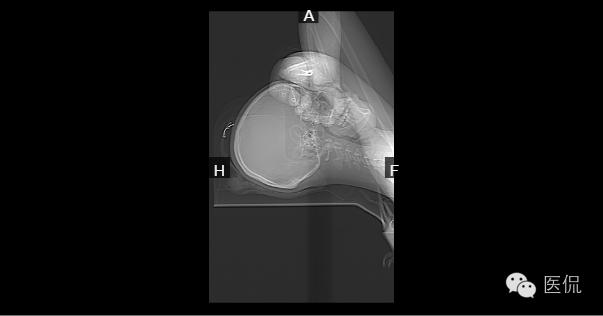

病例一

患者信息:女,18岁

检查部位:l

检查方法:L3--S1椎间盘平扫

患者主诉:腰疼1年余

影像所见:

胸腰段生理性曲度以L1、2为中心后突,L1~椎体前缘见椎缘骨,各椎间隙未见明显狭窄;横断位:L4-5、L5-S1椎间盘朝后突出,相应硬膜囊前缘受压;黄韧带不增厚;L5-S1右侧椎间小关节面增生、硬化,间隙狭窄,椎旁软组织未见异常。

诊断意见:

1、腰椎生理曲度后突。

2、L4-5、L5-S1椎间盘突出(后中央型)。